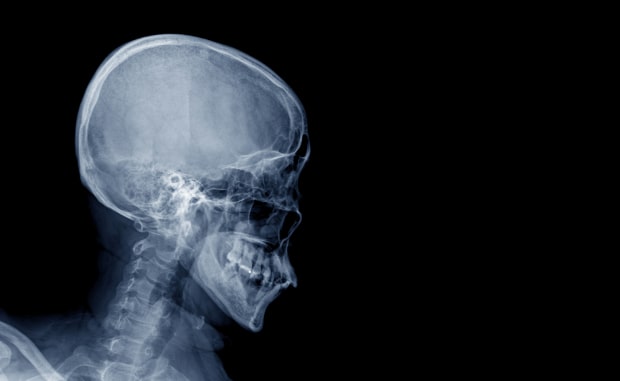

Рентгенография черепа

Рентгенография черепа в 2-х проекциях – это метод исследования, который позволяет диагностировать или уточнить значительное количество неврологических заболеваний.

Выполнить рентгенографию черепа в 2-х проекциях (прямой и боковой) в Казани вы всегда можете в медицинской клинике «Звезда». Врачи нашего центра проведут исследование быстро и по приятной для вас цене.